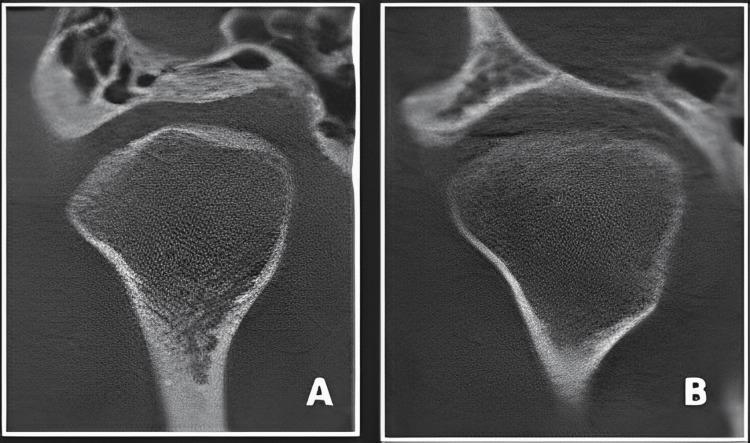

Background Temporomandibular joint disorders (TMD) represent a prevalent group of conditions impacting the temporomandibular joint. Among the therapeutic interventions, occlusal splint therapy has gained recognition for its potential to address TMD symptoms, particularly in cases involving joint displacement. Objective This study aims to investigate the effectiveness of occlusal splint therapy in cases of moderate TMD with joint displacement, focusing on changes in condylar position, joint morphology, and patient-reported outcomes. Methods A retrospective analysis was conducted involving 148 participants who underwent occlusal splint therapy between January 2018 and December 2020. Data were collected through cone beam computed tomography (CBCT) imaging for precise assessments of condylar position and joint morphology. Ethical approval was obtained, and participants provided informed consent. Baseline characteristics, medical history, and TMD severity were recorded. Occlusal splint therapy included individualized fabrication, occlusal analysis, adjustments for optimal fit, and prescribed wear schedules. Follow-up included CBCT scans at specified intervals (three months and six months), with participant-reported outcomes collected. The data analysis was conducted using IBM SPSS Statistics for Windows, Version 22.0 (Released 2013; IBM Corp., Armonk, NY, USA). Paired t-tests or nonparametric equivalents were employed to assess changes in condylar position and joint morphology. Subgroup analyses were conducted to explore potential factors influencing treatment outcomes. The significance level was set at p < 0.05 for all statistical tests. Results The entire cohort (n = 148) had a mean age of 32.5 years (± 8.1), with a balanced gender distribution. Changes in condylar position revealed a statistically significant improvement (p = 0.03), with a mean decrease of 0.2 mm posttreatment. Joint morphology changes indicated increased joint space width (p = 0.01), improved disc position (p = 0.02), and nonsignificant alterations in bony structures (p = 0.10). Patient-reported outcomes demonstrated significant improvements in pain levels, jaw functionality, and satisfaction (all p < 0.001). Age and gender subgroup analyses showed consistent improvements in condylar position, joint morphology, and patient-reported outcomes across different groups. Conclusion Occlusal splint therapy demonstrated effectiveness in improving condylar position, joint morphology, and patient-reported outcomes in cases of moderate TMD with joint displacement. The findings underscore the potential of occlusal splint therapy as a viable intervention for managing TMD, providing valuable insights for clinicians and researchers.

整个队列(n = 148)的平均年龄为32.5岁(± 8.1),性别分布均衡。髁突位置的变化显示出统计学上的显著改善(p = 0.03),治疗后平均下降0.2毫米。关节形态变化表明关节间隙宽度增加(p = 0.01),盘位置改善(p = 0.02),骨结构无显著改变(p = 0.10)。患者报告的结果显示疼痛水平、下颌功能和满意度有显著改善(均p < 0.001)。年龄和性别亚组分析表明,不同组在髁突位置、关节形态和患者报告的结果方面均有一致的改善。